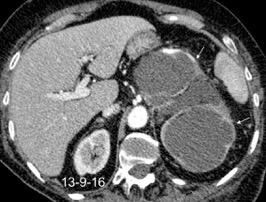

27. DERRAME PLEURAL IZQUIERDO. URINOMA

Enfermedad subdiafragmática Urinoma

Raro. Trasudado.

Orina en espacio pleural

Causas en 78 casos

Trauma……..66

Postcirugía 16

Obstrucción…21 aguda con cálculo e hidronefrosis..12

Freitas A et al. Pleural Effusion Secondary to Obstructive Uropathy: A Case of Urinothorax. Eur J Case Rep Intern Med. 2020/ Toubes ME et al. Urinothorax: a systematic review. J Thorac Dis 2017;

Hidronefrosis con cálculo ureteral